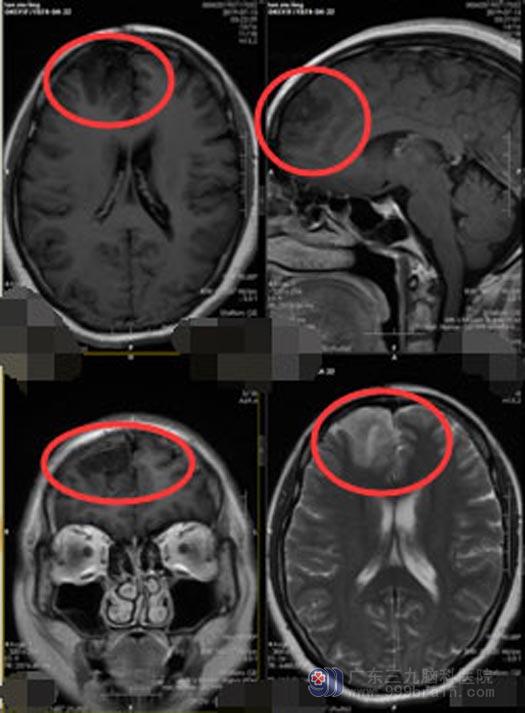

在广东三九脑科医院神经外五科进一步MR平扫+增强等检查,诊断:1.右侧额叶占位:少突胶质瘤?弥漫性星形细胞瘤?医生告诉谭阿姨:脑肿瘤除了头痛、恶心、呕吐等常见症状,有些肿瘤患者会出现其它的伴随症状,据文献报道,其发生率可高达25%~40%,有时可表现为傻笑、语言错乱、定向障碍、缺乏自制力等。

▲手术前